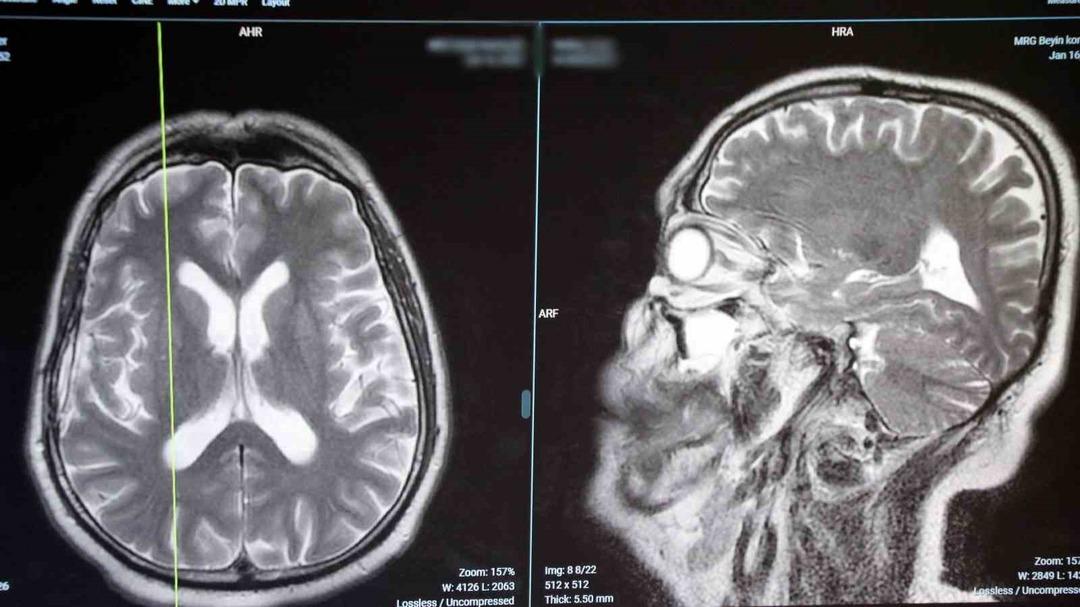

“Koku bozuklukları beyin kanseri, epilepsi ve parkinson gibi hastalıkların bir belirtisi olabilir”

Hastalardan en yaygın şikayetler yaprak döken meyveler, kokmuş sebzeler, bayat yiyecekler ve Demyrele’yi ifade eden tuvalet kokusu, “migren saldırısı sırasında nörolojik terimler, kokuların kokusunu görebilir veya baş ağrısından önce görebileceğimiz baş ağrısının başlamasından önce. Beyin tümörleri gözlenmiştir.